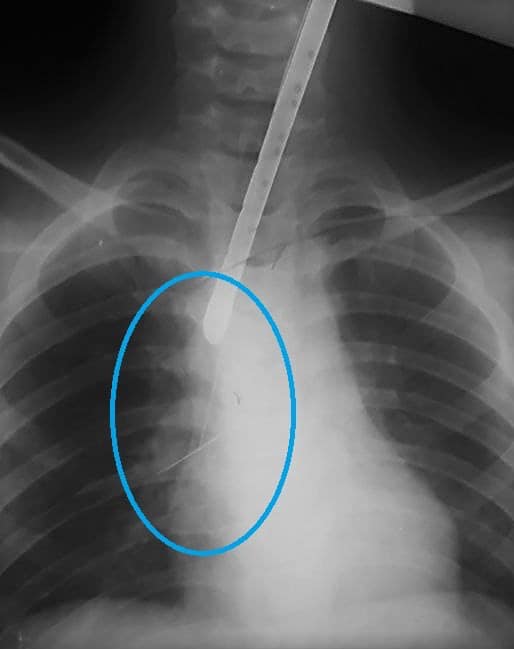

Как сообщают сотрудники Днепропетровской областной детской больницы, вечером 28 октября к ним привезли ребенка, который по неосторожности проглотил булавку. Чтобы выяснить, где именно находится инородный предмет, врачи провели при помощи эндоскопа (осветительно-оптического прибора) исследование горла ребенка. В итоге они обнаружили, что швейная шпилька прикололась к трахее. Выглядело это так:

Медики попытались втащить булавку из ребенка при помощи специальной петли, но булавка начала острой частью спускаться вниз по дыхательным путям к правому бронху и подкалываться к нему.

В Днепре спасали ребенка, который проглотил булавку/ фото: facebook.com/Дніпропетровська обласна дитяча лікарня В Днепре спасали ребенка, который проглотил булавку/ фото: facebook.com/Дніпропетровська обласна дитяча лікарня

Несмотря на то, что врачи захватили петлей инородный предмет (удерживали от падения вниз), продолжать его извлечение таким способом они побоялись. Из-за малейшей  неосторожности можно было травмировать бронх, что привело бы к кровотечению. Специалисты обговорили все возможные варианты выхода из сложившейся нестандартной ситуации и пришли к не менее нестандартному решению. Так, они ввели гибкий бронхоскоп через жесткий бронхоскоп и осторожно – практически не повредив слизистую бронха и трахеи – достали им злосчастную булавку из тела маленького пациента. Потому его не пришлось срочно оперировать.